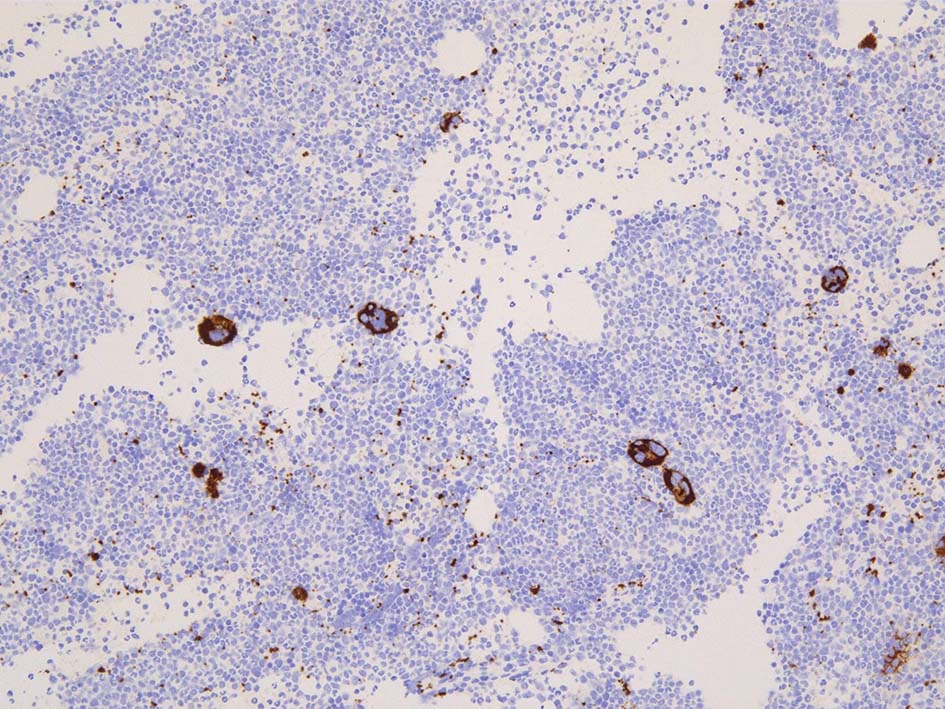

免疫染色; CD34, c-KIT, p53染色

本症例ではCD34, C-KIT陽性幼若細胞が増加している. 芽球はcountで4.3%. CD34, C-KITではfocalに 5-10%.

p53は核陽性細胞がごく少数認められた. 核淡染細胞は増加している. p53の変異を調べる必要がある. (有意な増加といえるか?)